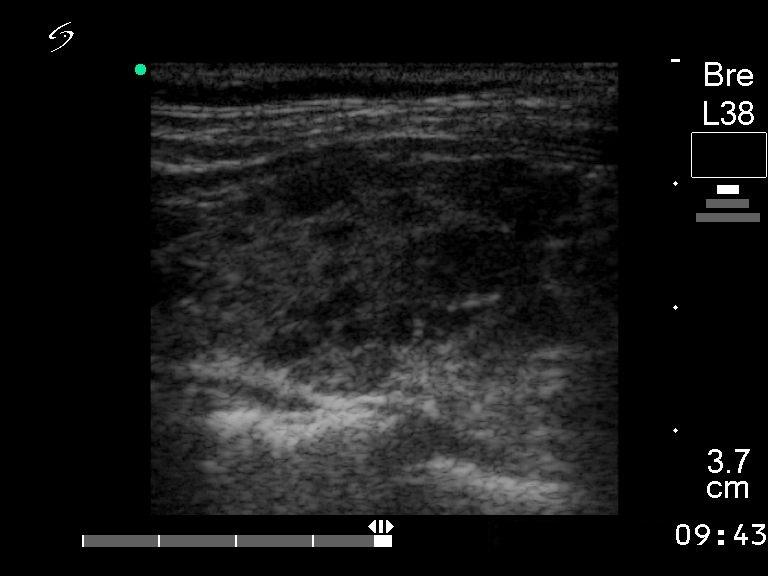

Follow-up examination 5 years later (third row of images):

Clinical presentation: the replacement therapy had been stopped for two years because the patient's cardiologist suspected the levo-tiroxine treatment worsening hypertension.

Functional state: euthyroidism (TSH 4.08 mIU/L).

Ultrasonography: the size, the echo pattern of the thyroid, i.e. the echogenicity index, the location of hypoechogenic fields were almost identical to that seen for 5 years.

Suggestion TSH-test every year.